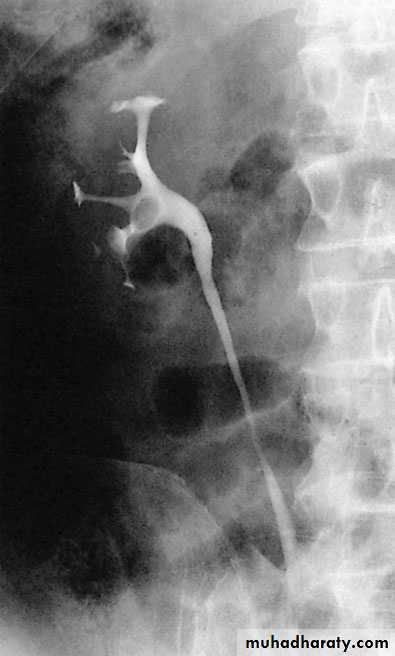

IVU needs Patient PreparationRETROGRADE PYELOGRAPHY

Opacification of the ureter and pelvicalyceal system by the retrograde injection of contrast media using ureteric catheter.Indications

Employed after an excretory urogram that inadequately visualized the anatomy of the upper tract.when there are contraindications to do IVU

Retrograde ureterogram demonstrating the collectingsystem with radiolucent filling defect in the renal pelvis.